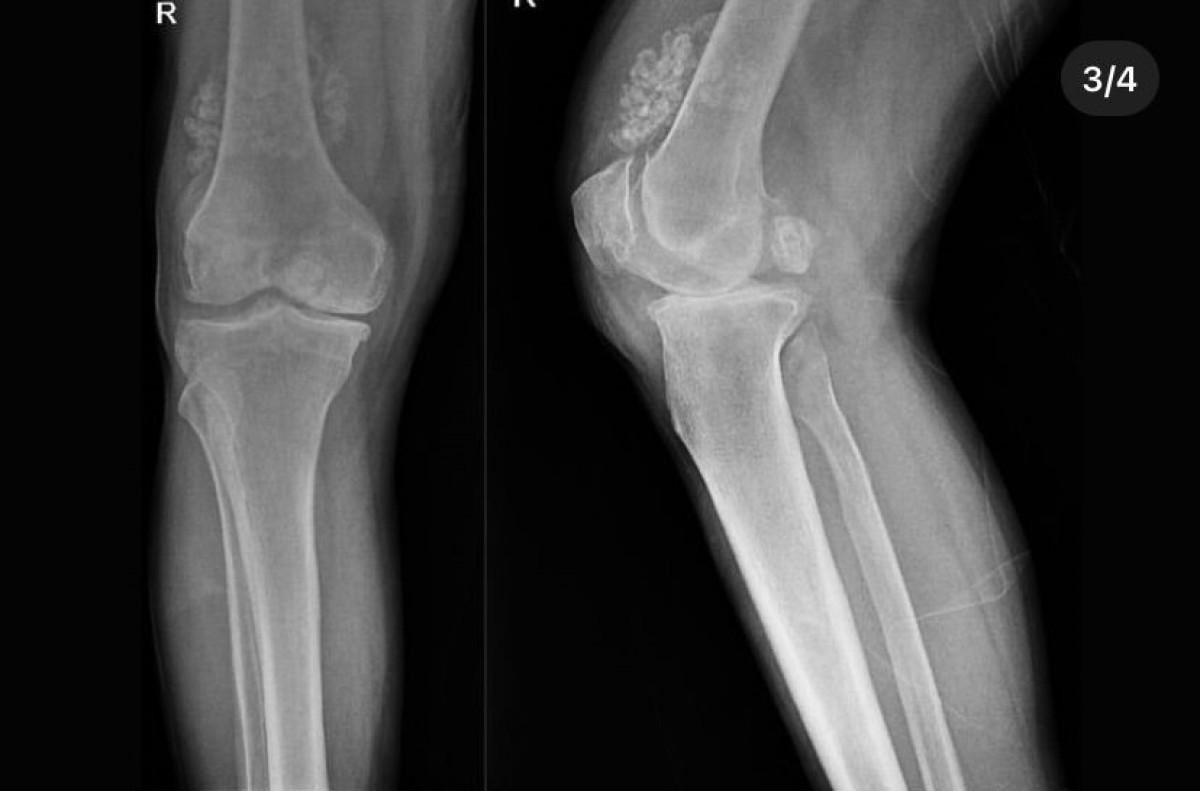

Doktorlar, Düzce Üniversitesi Tıp Fakültesi Hastanesi'nde tedavi gören hastanın diz eklemi çevresinde "multipl sinovial kondromatozi" gördü.

Bunun üzerine ameliyata alınan hastanın dizinden 41 adet eklem faresi de denilen kemik parçası çıkarıldı.

Özellikle diz eklemi çevresinde görülmekle birlikte kalça, dirsek ve diğer eklemlerde de görülen, ufak parçalardan oluşan cisimler olarak tanımlanan eklem faresi, eklem çevresinde eklem sıvısı ya da sinoviyumda görülen kıkırdak ya da kemik parçalarıdır.

Eklem farelerinin boyutları birkaç milimetreden birkaç santimetreye kadar çıkabiliyor.